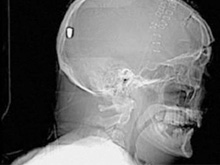

В Британии врачи нашли у пациента пулю в голове13.05.10 13:07 Прочтений новости 1174 Общество В Британии у пациента, который поступил в клинику с подозрением на инсульт, врачи обнаружили пулю в голове. Но остается неизвестным, как мужчина получил ранение.Рентгеновские снимки головы показали, что в полости черепа находится инородный предмет. Мужчине сделали томографию головы, и врачи установили, что этим предметом является пуля. Как сообщается, 19 апреля 61-летний Питер Хесфорд упал во время работы у себя в саду. Позже его обнаружила жена, которая вызвала скорую. Мужчина оставался в сознании, но не мог говорить. Медики, прибывшие на место, заподозрили у Питера Хесфорда инсульт и доставили его в Больницу Уитеншо. Эксперты по баллистике, изучив снимки пациента, пришли к выводу, что пуля, застрявшая в затылочной области, могла попасть туда через глаз. Но мужчина не помнит, что именно с ним произошло. Врачи попытались удалить пулю, однако это оказалось невозможным из-за ее положения по отношению к окружающим структурам. Пациент остается в больнице, а его состояние расценивается как стабильное. Комментарии (всего 0)